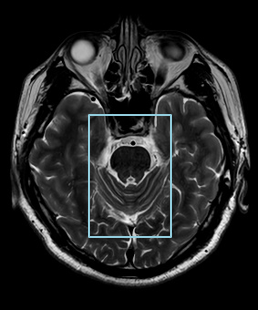

在磁共振领域,深度学习技术对图像进行降噪、上采样、减轻振铃伪影的处理,带来了清晰且细节丰富的图像。

过去,高分辨率图像的获取往往伴随着漫长的扫描时间,这影响了图像获取的效率,对于危重疾病的快速诊断是一大挑战。然而,PIQE技术的出现彻底颠覆了这一局面。此次发布的全新3T磁共振Galan Supreme,搭载全新的自研磁体和梯度线圈,并深度融合PIQE技术,可以实现在不增加扫描时间的前提下,轻松获取到高分辨率的图像,为临床带来了兼具高效与高质量的影像体验。